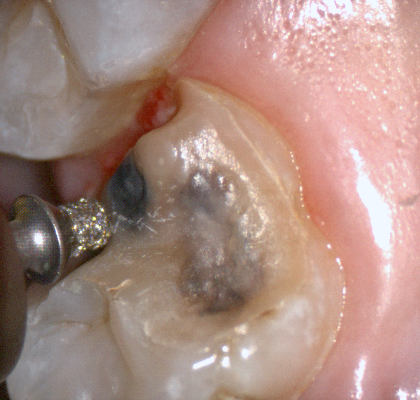

The following pictures depict the sequence of burs we recommend that you use to finish a preparation quickly. While patient is getting numb, take a quick look at the clearance you will need to reach proper material thickness. Once the quadrant is isolated with isolite and optragate, take an occlusal router bur and create a trough to gain the proper depth. Follow that with a flat disk, and you can quickly reduce the occlusal height.

A shoulder bur of .8 mm thickness can help you reduce the interproximal areas as well as the buccal and lingual margin lines. Before finishing the prep, place hemostatic agent like expasyl in the sulcus and place retraction cord. while it is setting, check your reduction. If you need more space, now is the time to reduce some more.